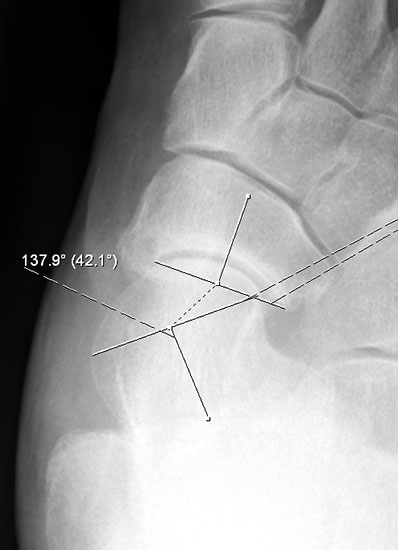

Der Talo-Metatarsale I Winkel bzw. die laterale talonaviculare Subluxation auf der stehenden dorsoplantaren Aufnahme des Fuβes dokumentieren das Ausmaβ des Vorfuβ abductus (Abb. 6 a,b). Ein dp Talo-Metatarsale I Winkel von > 10° (nach medial konvex) ist als pathologisch anzusehen. Mit der Bestimmung der talocalcanearen Divergenz (Abb. 6 c) erhält man ein Eindruck über das Ausmaβ des Rückfuβ valgus; eine leichte Divergenz bis ca. 12° gilt als physiologisch 20.